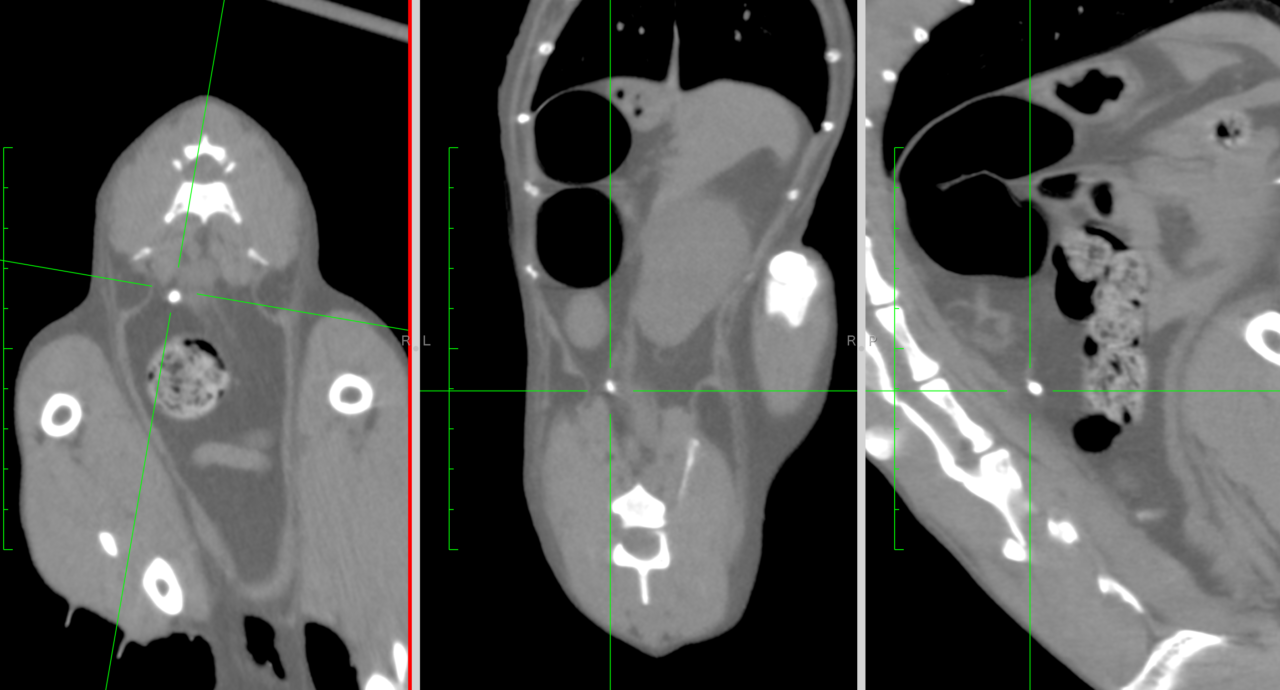

高齢の猫さんがかかりつけで慢性腎機能障害の治療中に急に腎数値が上昇したとのこと。精査を希望されて来院しました。CTで精査を行うと両側の尿管結石が確認され、顕微鏡下で両側の結石を摘除しました。術後数日は腎数値が改善しませんでしたが10日目頃より徐々に数値の改善とともに元気も出てきました。高齢ながら頑張ってくれました。